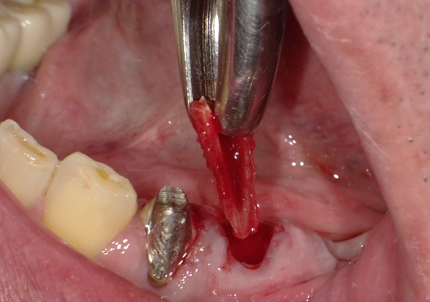

3. 右上1番・左上2番 SST(ソケットシールドテクニック)

【右上1番SST 口蓋側歯根の抜歯】

【左上2番 SST 口蓋側歯根の抜歯】